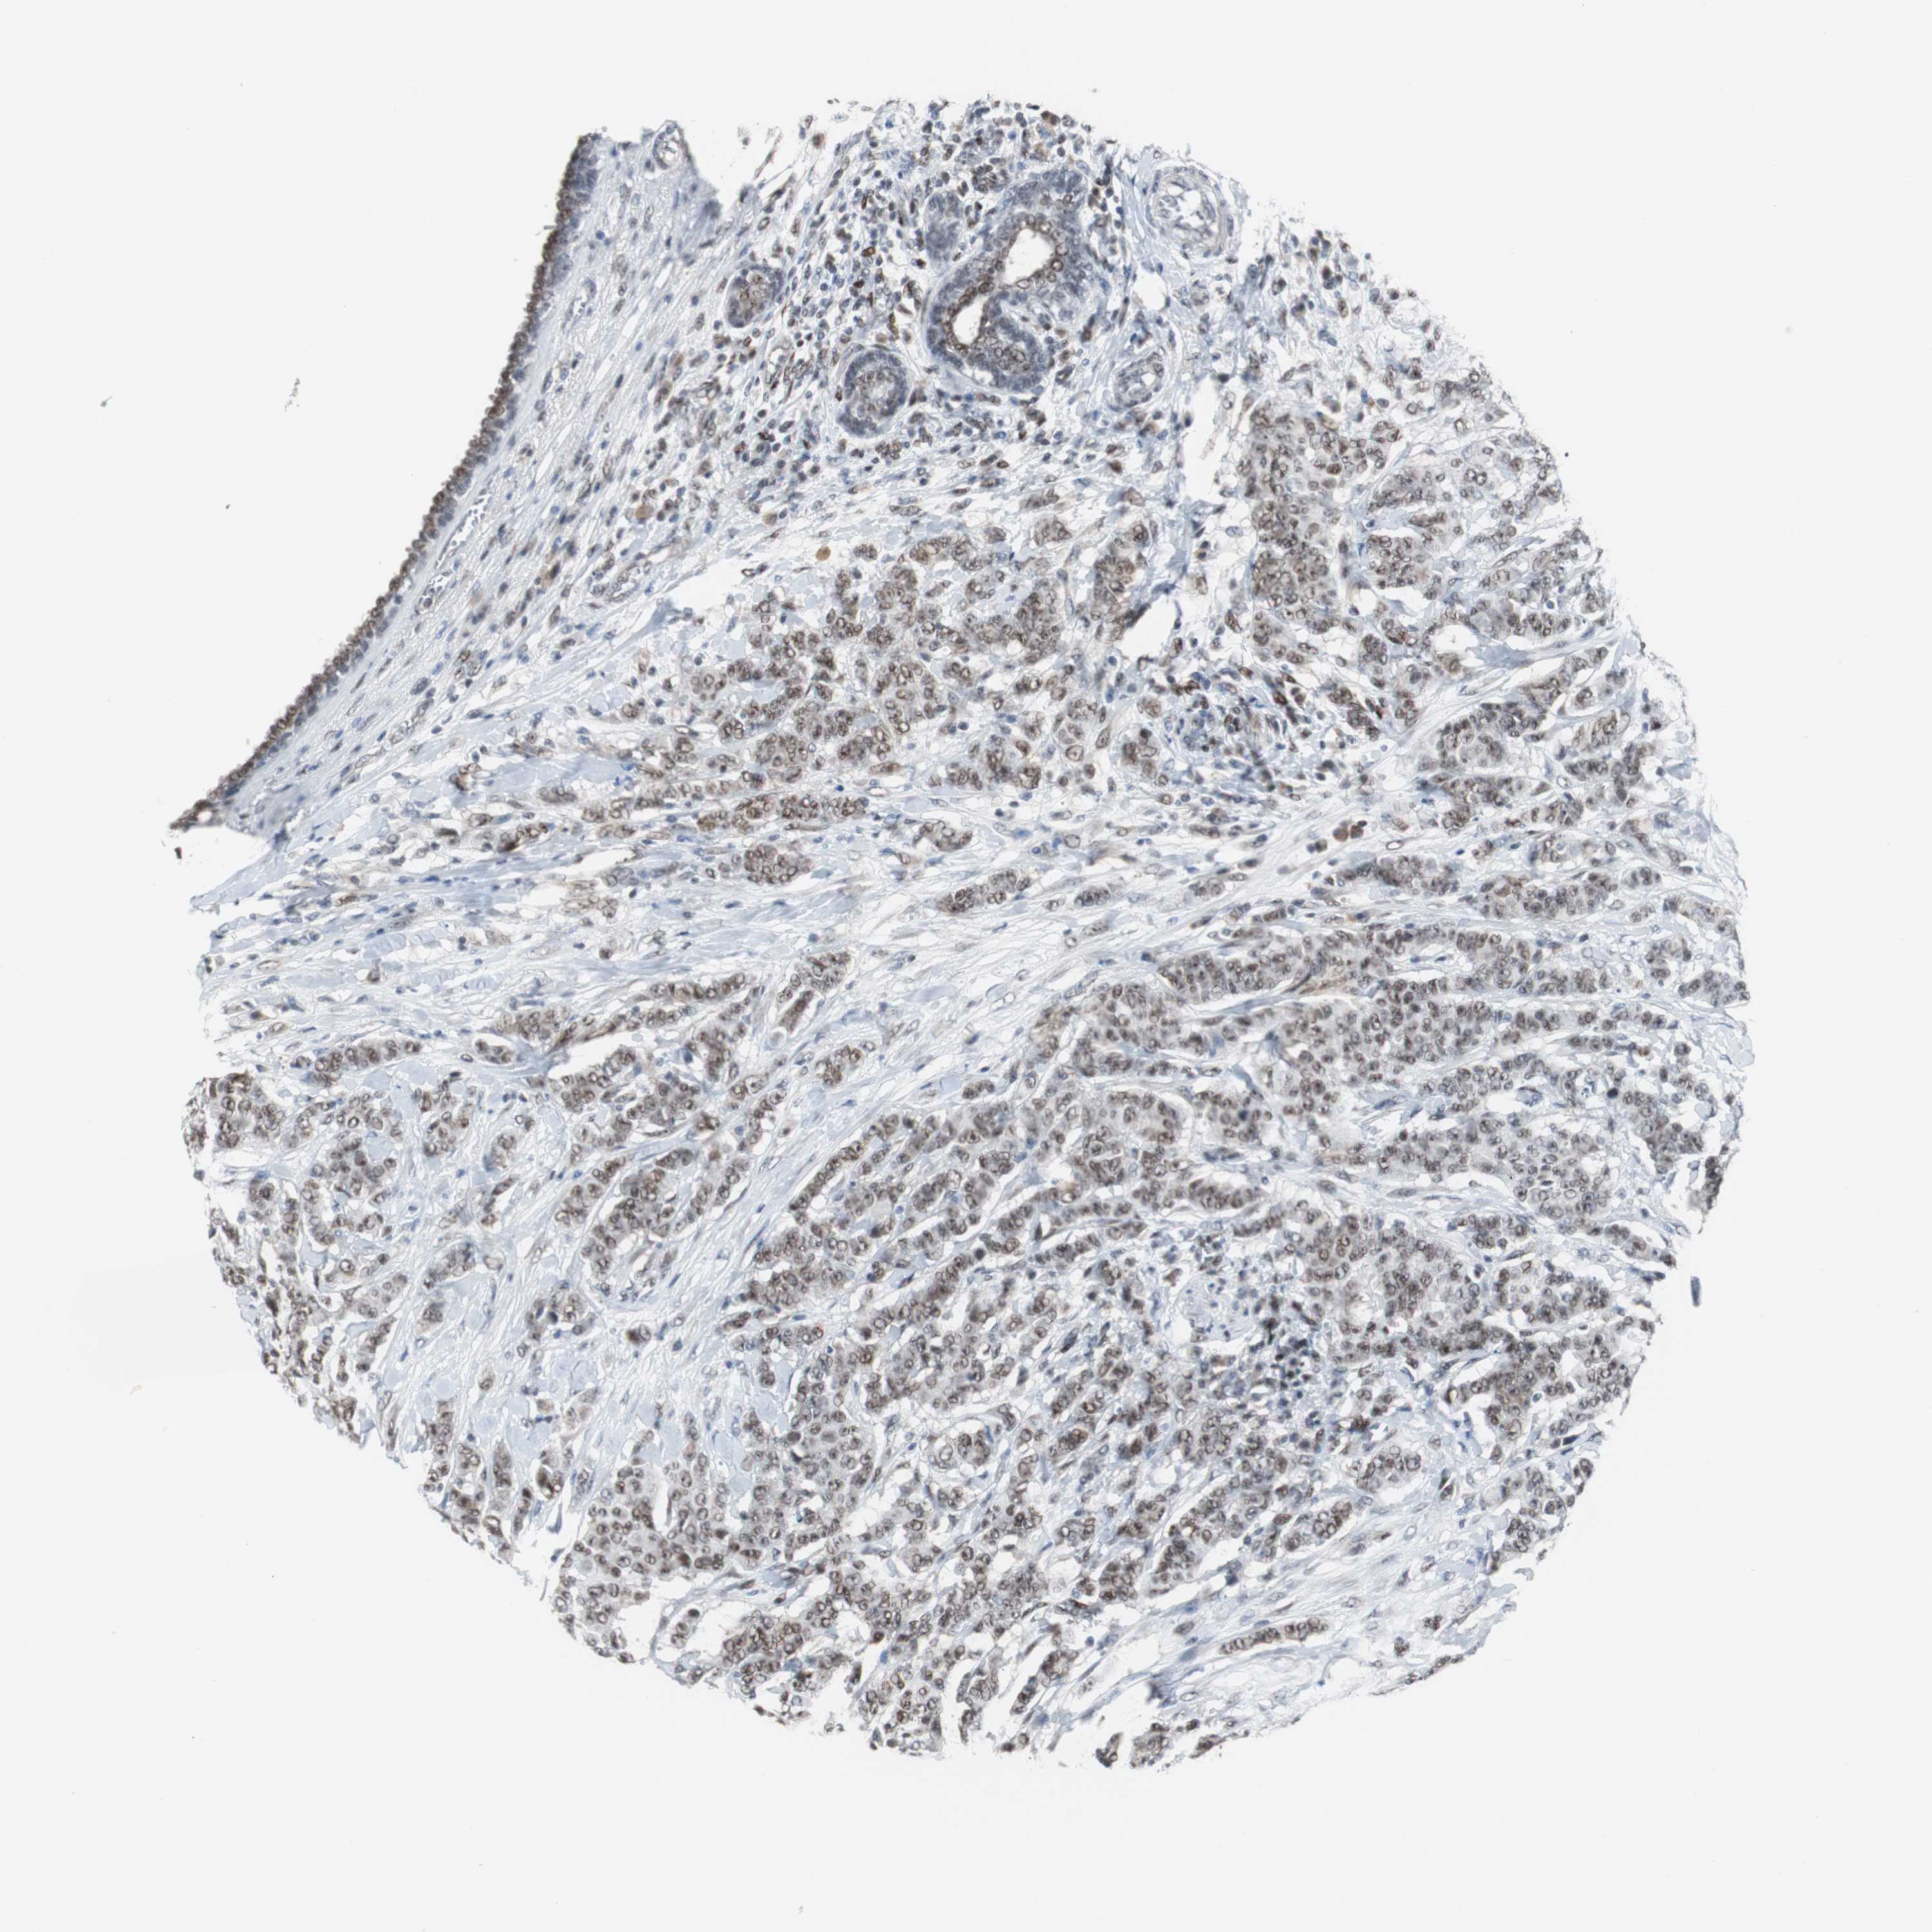

BRCA TCGA BRCA VALIDATION PROTEIN EXPRESSION

Breast cancer

Human cancer

Breast invasive carcinoma